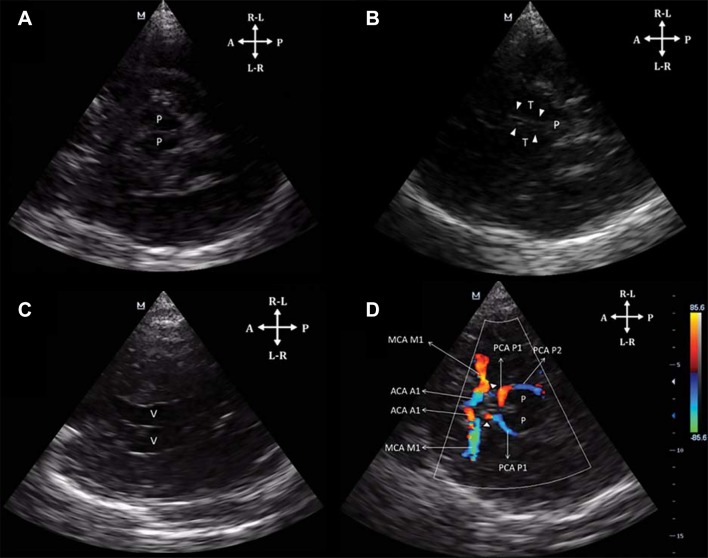

Similar to TCD, the transtemporal is the main window and thus the first performed. In the transtemporal window, three main planes are recognized using TCCS: the mesencephalic, the diencephalic and the ventricular plane. The mesencephalic plane is characterized by central hypoechoic butterfly-shaped cerebral peduncles, surrounded by the hyperechoic basal cisterns (Fig. 11a). Angulating ten grades cephalad, the diencephalic plane is now recognized by the central two hyperechoic line corresponding to the third ventricle, the hypoechoic thalami on each side of the third ventricle and the hyperechoic pineal gland (Fig. 11b). With further cephalad angulation, the ventricular plane is now demarcated by the frontal horns of the lateral ventricles (Fig. 11c). The mesencephalic and diencephalic planes are commonly used for vascular diagnosis, because in these planes the Circle of Willis is found [15, 25] (Fig. 11d).

Fig. 11.

a TCCS from a transtemporal view on the mesencephalic plane. P cerebral peduncles; b TCCS from a transtemporal view on the diencephalic plane. The double hyperechoic line corresponds to the third ventricle (arrowheads); T thalami, P pineal gland. c TCCS from a transtemporal view on the ventricular plane. Both lateral ventricles (v) are visualized. d Color Doppler demonstrating the vessels of the Circle of Willis. ACA anterior cerebral artery, A1 precommunicating, MCA middle cerebral artery, M1 mainstem; PCA: posterior cerebral artery with P1: precommunicating and P2: postcommunicating segments. Posterior communicating arteries (arrowheads)

(Reproduced with permission from [25])